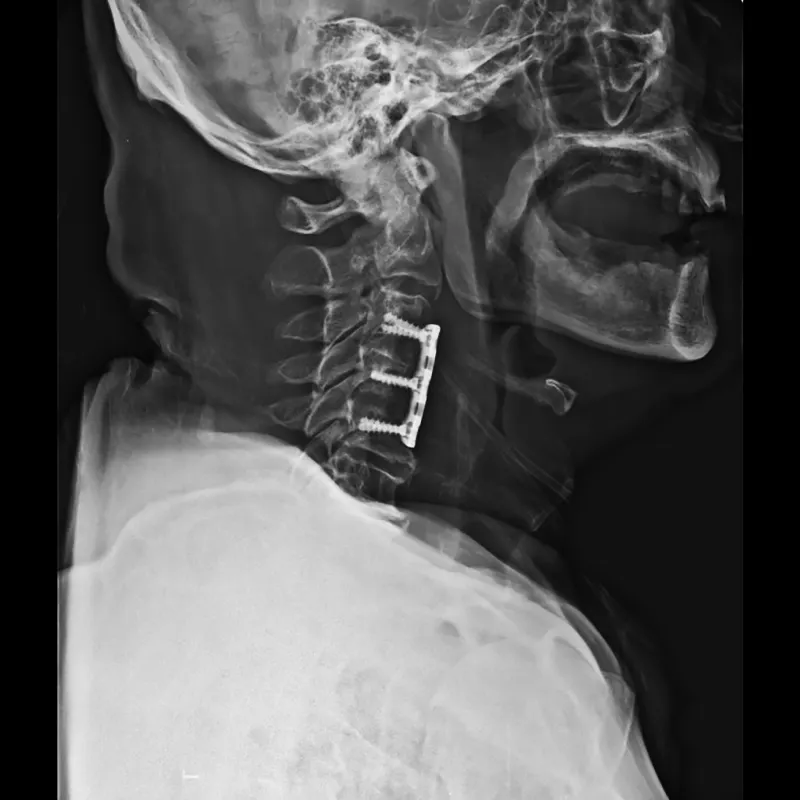

Anterior Cervical Discectomy And Fusion With Cage

Anterior Cervical Discectomy And Fusion With Plating